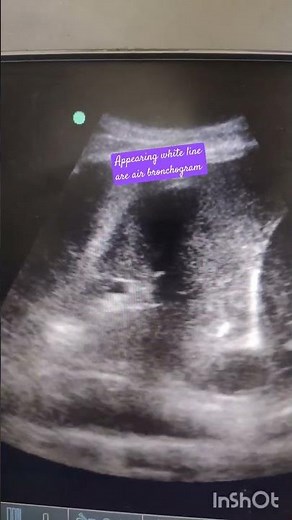

Air bronchogram in lung ultrasound

Air Bronchogram 2